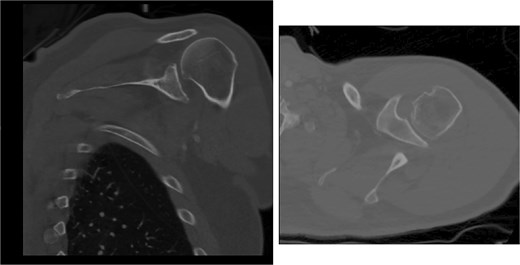

Both shoulders were reduced urgently by the orthopedic team, with immediate improvement in paresthesias (Fig. 2). Post-reduction CTs were significant for bilateral chronic rotator cuff disease with superior migration of the humeral heads, right-sided supraspinatus and subscapularis atrophy, and a left nondisplaced glenoid fracture (Figs 3 and 4). He was discharged home in bilateral slings.

Post-reduction CT of the left shoulder demonstrating superior humeral head migration relative to the glenoid.

Post-reduction CT of the right shoulder demonstrating superior humeral head migration relative to the glenoid, visualized evidence of prior rotator cuff repair surgery, and a nondisplaced anterior-inferior glenoid fracture.